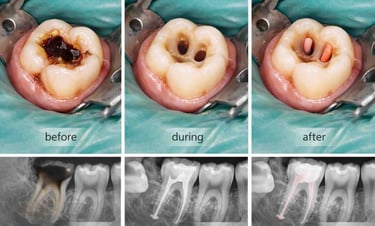

Root canal treatment removes infected or damaged pulp from inside a tooth. The pulp contains nerves and blood vessels, and infection can cause pain, swelling, or abscesses. During the procedure, the dentist cleans out the infection, shapes the root canals, and fills them with a safe material. Finally, the tooth is restored with a crown or filling to protect it. Root canals prevent infection from spreading and help keep your natural tooth

Examination & X-rays – determine the extent of infection or damage

Cleaning the pulp – remove infected tissue from inside the tooth

Shaping & filling – shape canals and fill with biocompatible material

Temporary or permanent restoration – crown or filling placed to protect the tooth